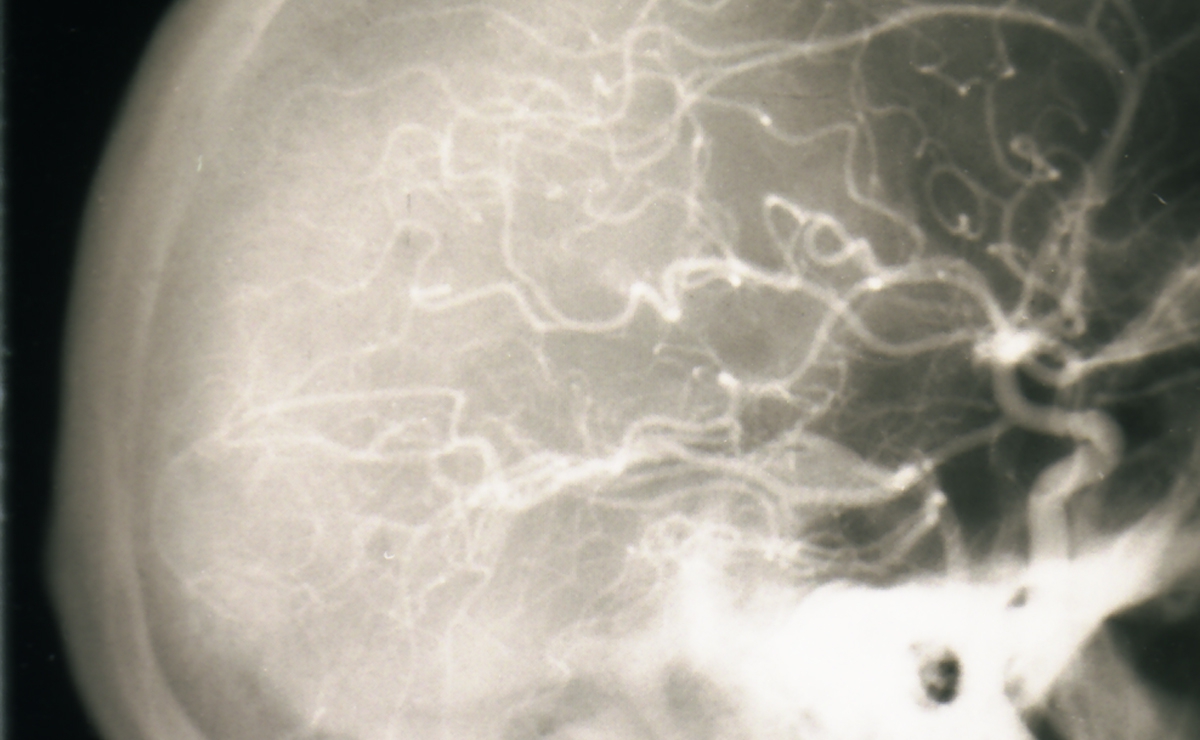

Neurorradiología, Electroencefalografía, Electromiografía